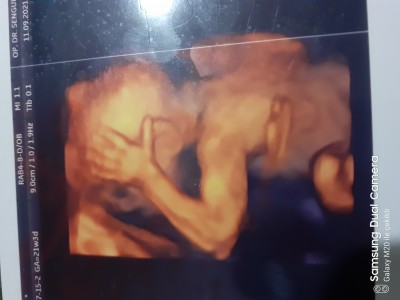

Kızlar 29+0 oldum gittiğim hastanede renkli ultrason yok bir de doktor  bu haftaya kadar sürekli poz vemiyor dedi durdu beni sinir etti güç bela bir bir fotoğrafını aldım siyah beyaz onda da sırtı dönük yüzü görülmüyor.

Ya çok merak ediyorum yüzünü gözünü başka bir hastaneye gidip renkli ultrason fotoğrafı almak istiyorum sizce yüzünü gösterirse alabilir miyim. Bebeğim haftasına göre büyükmüş en son 26. Haftada 1200 gramdı. Yani yüzünü falan ultrasonda görebilir miyim sizce resmini alabilir miyim çok merak ediyorum neye kime benziyor diye :)

19. Haftada ozelde doktorum verdi canım. Buda benim.minnak oğlum telefonu sağa yatirip bak canim ceviremedim çünkü

Oyy maşallah nasıl da açık yüzü kime benziyor peki anlaşılıyor mu :) nasıl ekledin resmi ben de atayım

Bakar mısın benim görüntüye soruma ekleyebildim resmi ancak

Soruma baksana oraya ekledim bendeki tek resmi o